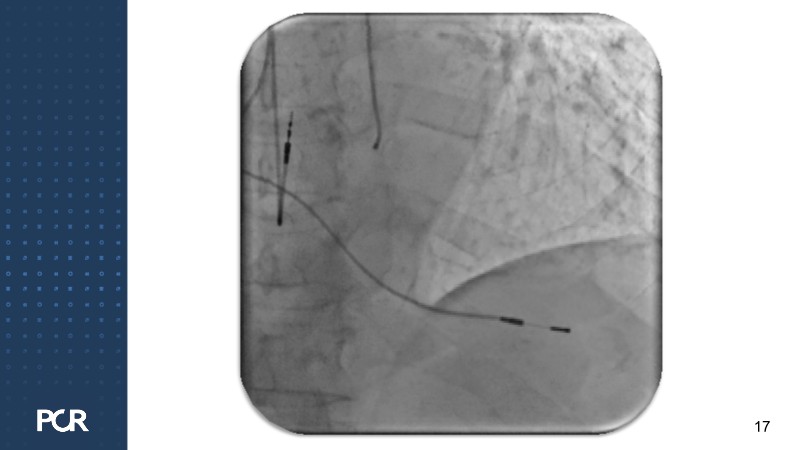

This session offers a comprehensive overview of the management of high bleeding risk (HBR) patients with multivessel disease. Through expert discussion and a live case demonstration featuring a complex elderly patient, it highlights how intracoronary imaging and physiology can guide procedural decisions and improve outcomes in this vulnerable population. The session also explores PCI strategies adapted to bleeding risk profiles, with a particular focus on the live case approach, including the use of sirolimus-eluting stents to optimise both procedural safety and long-term results.